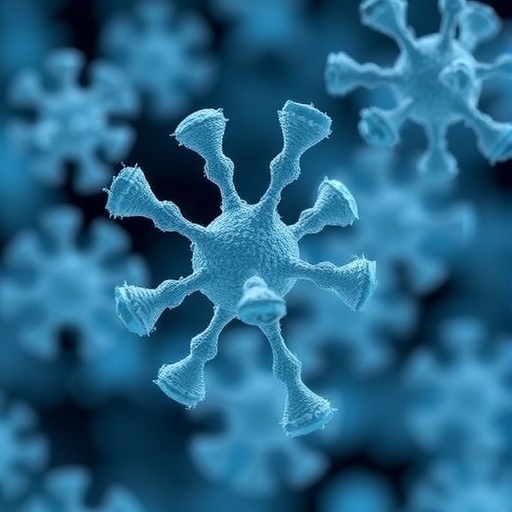

This transformative study, recently published in Nature Chemical Biology, details how laboratory-engineered antibodies can hone in on a structurally distinctive bacterial sugar, pseudaminic acid, effectively marking lethal pathogens for immune elimination. Such targeted specificity paves the way for treatments that could robustly combat drug-resistant bacteria, particularly those causing hospital-acquired infections that currently defy last-resort antibiotics.

At the heart of this breakthrough lies the sugar pseudaminic acid, a molecule absent in human cells but ubiquitous on the coats of various dangerous bacteria. This exclusivity designates pseudaminic acid as a highly selective immunotherapy target, dramatically minimizing the risk of off-target effects commonly seen with conventional antibiotics that can harm beneficial host cells.

The researchers ingeniously synthesized pseudaminic acid and its conjugated peptides in the laboratory, meticulously characterizing their three-dimensional molecular configuration. This precise molecular blueprint facilitated the rational design of a “pan-specific” antibody capable of recognizing pseudaminic acid across a broad spectrum of bacterial species and strains, highlighting the antibody’s remarkable versatility and clinical potential.

Image Credits: Stefanie Zingsheim/The University of Sydney